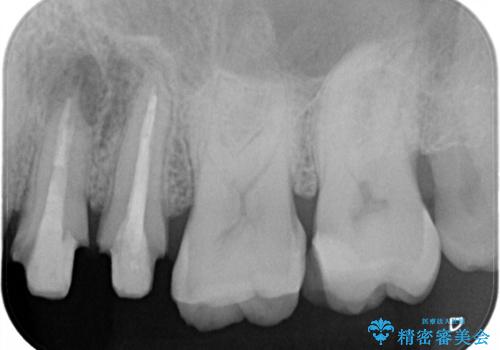

レントゲン上からも、歯の中(根管)が汚れている可能性があることをご説明したところ、根管治療からやり直しをすることになりました。

根管治療について

保険根管治療は回数がかかることが多く、終了予定がわかりにくいです。

当院では、根管治療は長い時間のご予約を頂き、多くの場合2~3回で終わります。

根管治療は歯内の治療なので患者様には見えない場所ですが、ここが細菌で汚染されると激しい痛みや長引く違和感の原因になります。

当院では、清潔な治療を徹底し、顕微鏡を使用した精密な治療を行っています。

症状や根管の状態により、治療金額が異なります(5~10万円目安)。治療回数による費用負担の増減はありません。